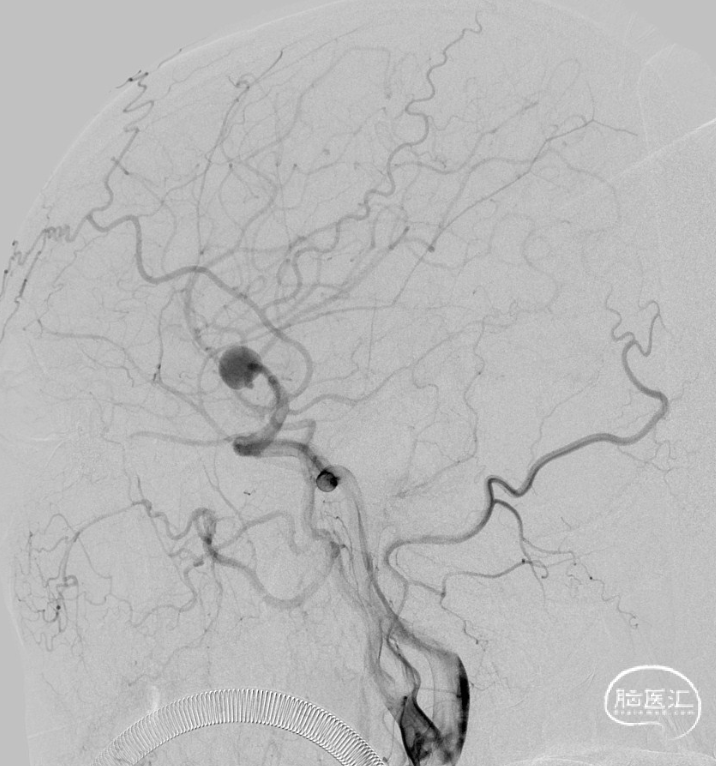

一期治疗

治疗经过